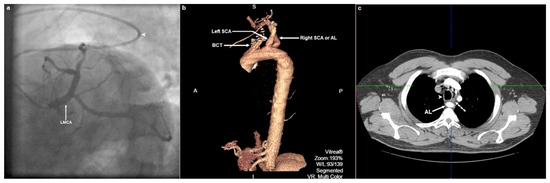

A 46-year-old male smoker, with a positive family history of premature coronary artery disease and a history of arterial hypertension and hyperlipidaemia was referred for coronary angiography because of episodes of stabbing precordial chest pain elicited by psychological stress and dyspnoea for the last 2 months. Serial electrocardiograms showed no signs of ischaemia and cardiac enzymes remained within normal limits. Transthoracic echocardiography was notable for suspected hypokinesia of the basal and mid inferior wall. Right transradial coronary angiography demonstrated widespread mild atheromatosis and suspected myocardial bridging of the mid left anterior descending artery. Scrutiny of the angiogram revealed a redundant course of a 5 Fr Judkins left 3.5 diagnostic catheter, which entered the aortic arch after it had formed a high-degree angulation at the right subclavian artery (SCA)-aortic arch junction. In a left anterior oblique caudal view, the peculiar catheter course resembled a slanted letter “Z” (Figure 1a). What do you suspect and what would you do next?

The redundant “Z-like” course of the Judkins left 3.5 catheter made us consider the possibility of an aberrant right SCA or arteria lusoria (AL). Targeted patient interrogation revealed that he had been experiencing dysphagia to solid foods and acid reflux symptoms for about 1 year. Subsequent multislice computed tomography (CT) angiography revealed an AL originating as the last branch of the aortic arch from a position located posterior and to the left of the origin of the left SCA, whereas the right and left carotid arteries were shown to arise from a common trunk (truncus bicaroticus) (Figure 1b; electronic supplementary material, video 1). Aneurysmal dilation of the proximal portion or the aortic origin of AL that would have been compatible with a Kommerell diverticulum was not shown. AL followed a retro-oesophageal course with evidence of oesophageal compression (Figure 1c). Our patient was referred for gastroenterological evaluation. Surgical vascular reconstruction should be considered in case of worsening dysphagia despite conservative measures.

Figure 1. Conventional invasive coronary and computed tomographic angiographic images. (a) Selective left coronary artery angiogram in the left anterior oblique caudal projection. Note, the Judkins left catheter angulation (arrowhead) just before the junction of arteria lusoria (AL) with the aortic arch where it traverses through a wider angle and curves back in order to enter the aortic arch and ascending aorta. Note, also that the course of the catheter from the proximal segment of AL up to the ostium of the left main coronary artery (LMCA) resembles a slanted letter “Z”. (b) Three-dimensional volume-rendered reconstruction of aortic multislice computed tomography (MSCT) angiography depicting a left aortic arch and an aberrant right subclavian artery (SCA) or AL originating distal to the origin the left SCA. A common trunk of right and left common carotid arteries (BCT; bicarotid trunk) is displayed as the first branch of the aortic arch. (c) Axial multiplanar reconstruction of aortic MSCT angiography depicting the oesophagus (dotted arrow) that is compressed between the trachea (arrowhead) and the dorsally located AL (solid arrow).